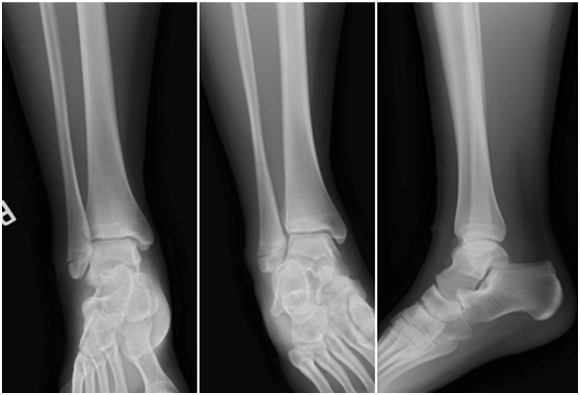

In August 2015, the fracture was re-evaluated, showing no improvement from previous radiographs (Figure 2). At this point, the patient was referred to the attending author for a second opinion. The fracture site remained swollen and painful. It was determined that the best treatment for the patient would be open reduction internal fixation of the fracture (ORIF) with bone grafting, as she had a non-union. Surgery was scheduled for September 2015.

Figure 2 Radiographs after 2 months of bone stimulator use. Anterior-posterior, Mortise and Lateral views of the right ankle. August 2015.